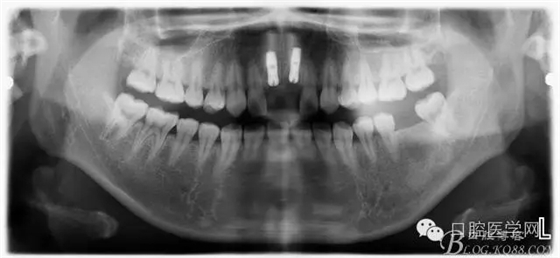

設(shè)計方案:11.21種植(選用登騰系統(tǒng),GBR植骨)12.22 RCT后樁冠修復(fù),牙齦瓷修復(fù)。

一期手術(shù)后3-6個月可做二次修復(fù),接愈合基臺,拆線后10-15天根據(jù)情況可以采模型做牙冠。